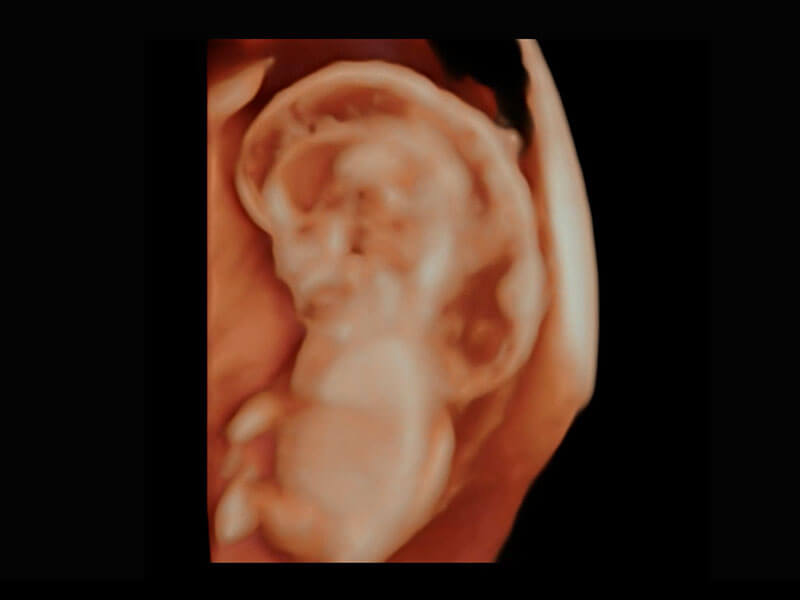

P60在胎儿早孕期超声筛查中为您带来优异的图像质量。

高分辨率容积成像-早孕胎儿

P60提供简单易学易用的高端诊断工具,为您中晚孕筛查提供快速清晰的解剖信息。